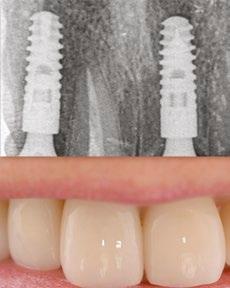

Imediátní implantace po extrakci

Okamžité zatížení implantátu